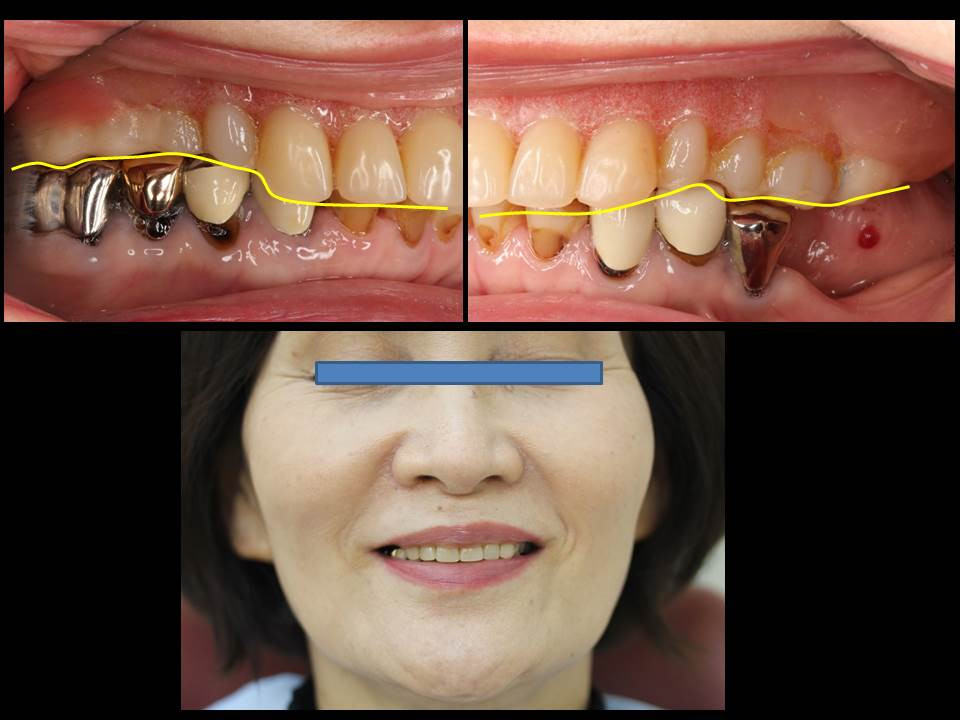

咬み合わせの不調和はお顔にも影響します。

術前のお口の中の様子②

奥歯にフォーカスを当てています。下の歯の被せ物も虫歯に罹患して黒くなっています。銀歯の欠点は、銀歯それ自体が黒く光り、むし歯になっていても患者様御自身だけでなく、専門家である歯科医師でもその中を透視して見ることができないため、むし歯を見落としてしまうことがあり、注意が必要です。

右上の画像ですが、奥歯が無い部分をそのままにしているため、噛み切った食べ物の流れが悪くなり、舌縁(舌の側面)に画像のように血豆や血袋が出来やすかったようです。